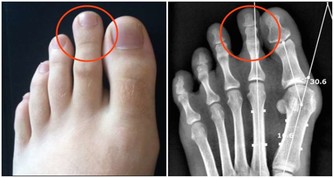

3、 尿酸

尿酸是人體產生的一種物質,這種物質一般在人體中濃度是一樣的,但是如果出現濃度升高的話,可能出現對身體有一定的危害,人體尿酸偏高會對腎臟造成一定的影響,出現痛風性腎病,早期僅表現為間歇性蛋白尿,但只是隨著病情的發展,晚期可發生腎功能不全,部分患者會出現尿酸性腎結石當結石引起梗阻時導致腎積水,腎盂腎炎,腎積膿等。通常腎不好的女性會臉色發黃,嘴唇蒼白,自然也就更加顯老了。